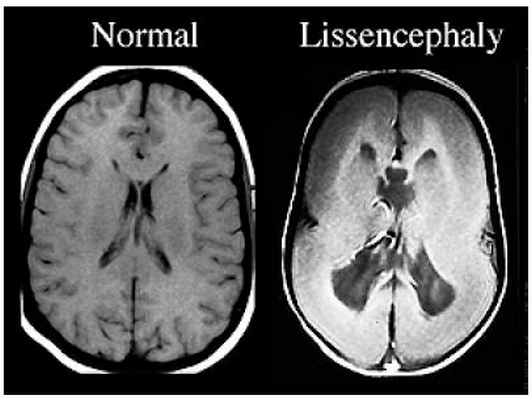

Лиссэнцефалия — редкая патология, функциональное нарушение работы головного мозга, вызываемое аномальным расстройством процесса образования новых нервных клеток в ЦНС у плода в конце второго триместра беременности. Лиссэнцефалия является результатом недостаточной миграции нейральных стволовых клеток из первичной нервной трубки. Развитие патологии приводит к тому, что головной мозг новорожденного имеет сглаженную поверхность без извилин. Дети с лиссэнцефалией значительно отстают в умственном развитии.

• Нарушения формирования коры, вызванные остановкой процесса миграции нейронов, которая приводит к появлению толстой четырехслойной коры и гладкой поверхности больших полушарий головного мозга

• Форма больших полушарий головного мозга в виде цифры «8» или песочных часов

• Усеченное ветвление белого вещества

• У новорожденного на Т2-ВИ могут быть выделены три слоя коры о Наружный клеточный слой → может быть относительно тонким и гладким

о Промежуточный слой с разреженным расположением клеток

о Более глубокий и толстый слой остановленных в процессе миграции нейронов, который имитирует ламинарную гетеротопию

• Локализация: задние > передние отделы полушарий головного мозга при мутации гена LIS1